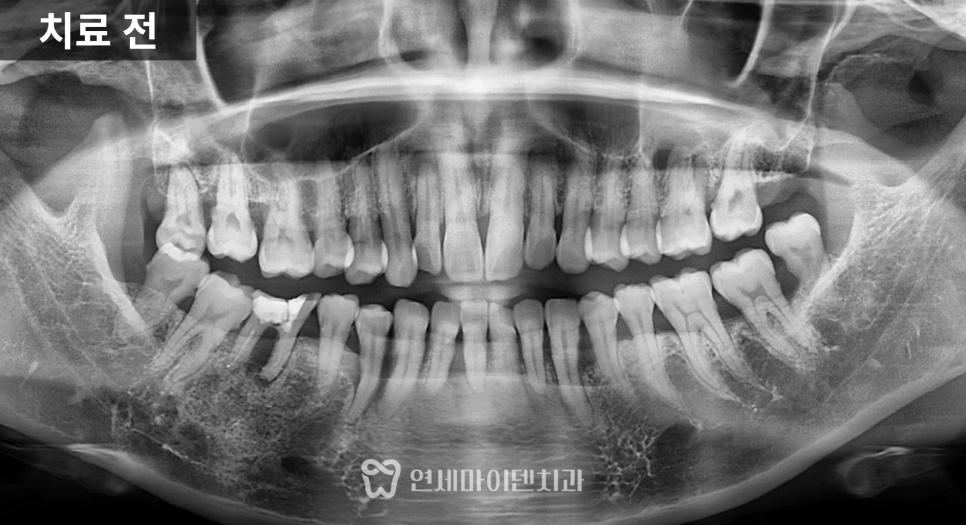

이번 환자분은 고령의 환자분이었습니다.

왼쪽 어금니가 빠진 뒤 장기간 방치되었고,

남아 있던 치아는

쓰러지고 흔들리는 상태였습니다.

반대편으로만 식사를 하다 보니

그쪽 치아에도 부담이 쌓여

결국 양쪽 모두 불편해진 상태였습니다.

치료 전 방사선 사진을 보면

치아가 쓰러진 문제도 있었지만

무엇보다 뼈의 폭과 높이가

많이 줄어든 상태

였습니다.

잇몸도 전반적으로 약했고,

반대편 역시 향후 치료가 필요할

가능성이 있는 상황이었습니다.